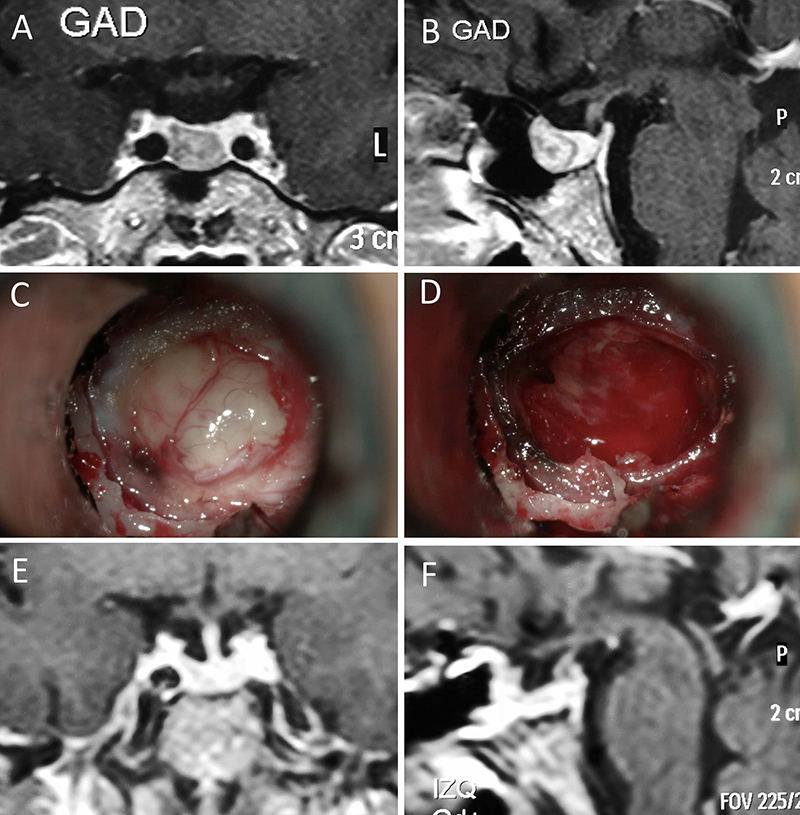

Figura 7: Acromegalia en mujer de 39 años. Con remisión bioquímica tras la cirugía. A-B: RM preoperatoria; C-D: intraoperatorio; E-F: RM postoperatoria.

Figura 8: Acromegalia en mujer de 50 años. Con remisión bioquímica tras la cirugía. A-B: RM preoperatoria; C-D: intraoperatorio; E-F: RM postoperatoria.